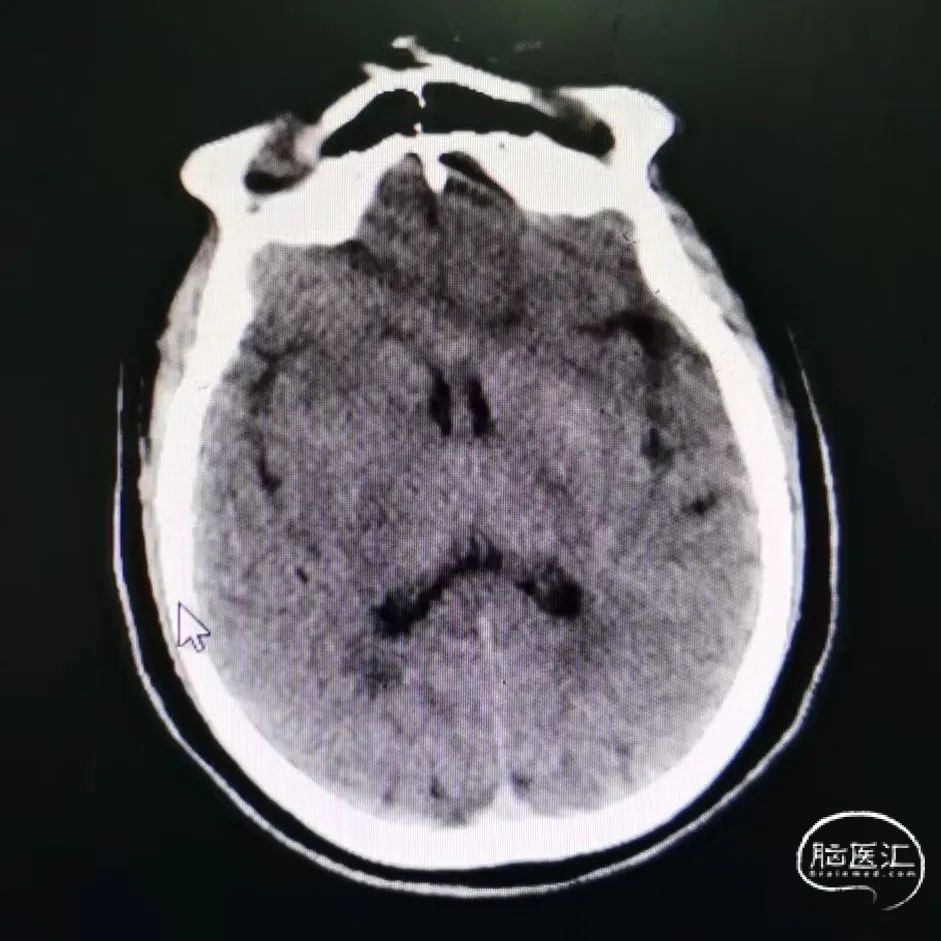

术后影像:

术后第1天,NIHSS 0分。